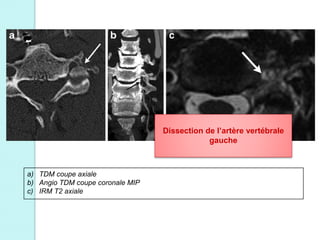

Fractures du foramen transverse :

Dissection traumatique de l’artère vertébrale

a) TDM coupe axiale

b) Angio TDM coupe coronale MIP

c) IRM T2 axiale

Dissection de l’artère vertébrale

gauche